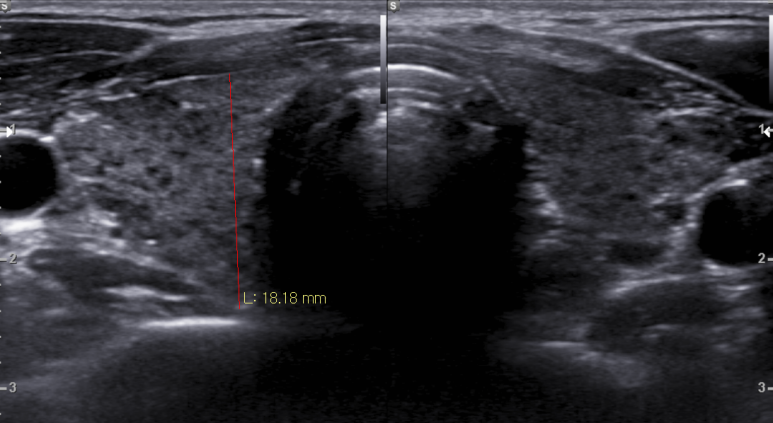

갑상선 초음파; 진행하는 갑상선염 소견과 동반된 크기 변화가 있는 림프절

https://blog.naver.com/ejercicio/220851532314 동대문구 답십리 우리안애, 우리안愛 내과, 초음파 클리닉, 영상의학 클리닉, 내과 전문의 전병연 #동대문구내과 #성동구내과 #광진구내과 #답십리역 #장안평역 #용답역 #청량리역 #신답역 #한양대역 #왕십리역 #답십리사거리 #촬영소사거리 #전농동사거리 #내과 #국가검진 #위내시경 #대장내시경 #갑상선초음파 #복부초음파 #경동맥초음파 #심장초음파 #암검진 #래미안위브아파트 #엘림스퀘어 #두산아파트 #동아아파트 #한양아파트 #동답한신아파트 #두산위브아파트 #힐스테이트청계아파트 #래미안미드카운티 #청솔우성 #래미안크레시티 #롯데캐슬노블레스 #e편한세상답십리아르테포레